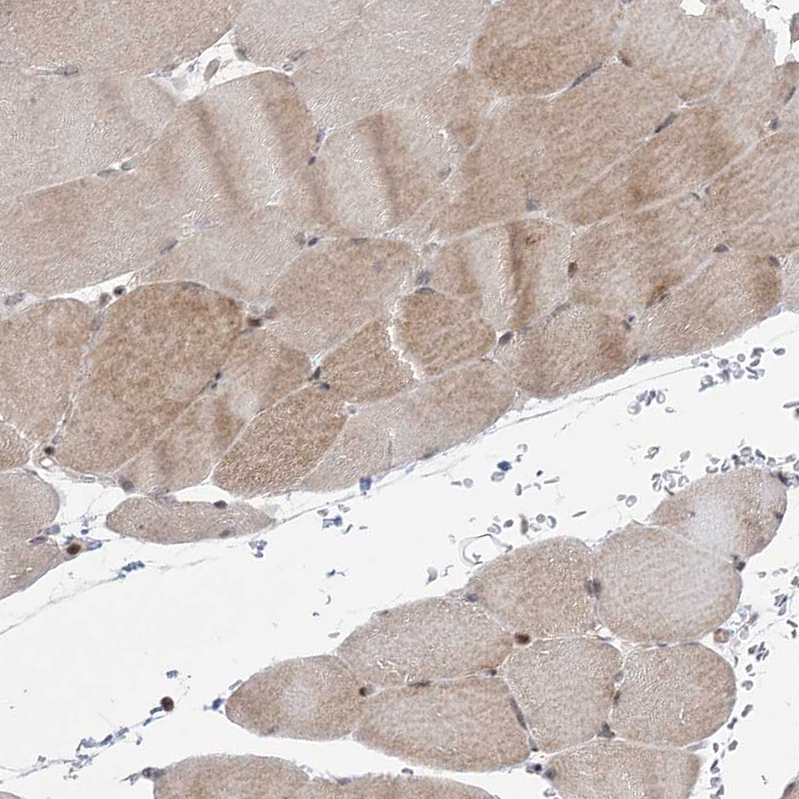

Immunohistochemical staining of human skeletal muscle shows moderate cytoplasmic positivity in myocytes in addition to weak nuclear positivity.